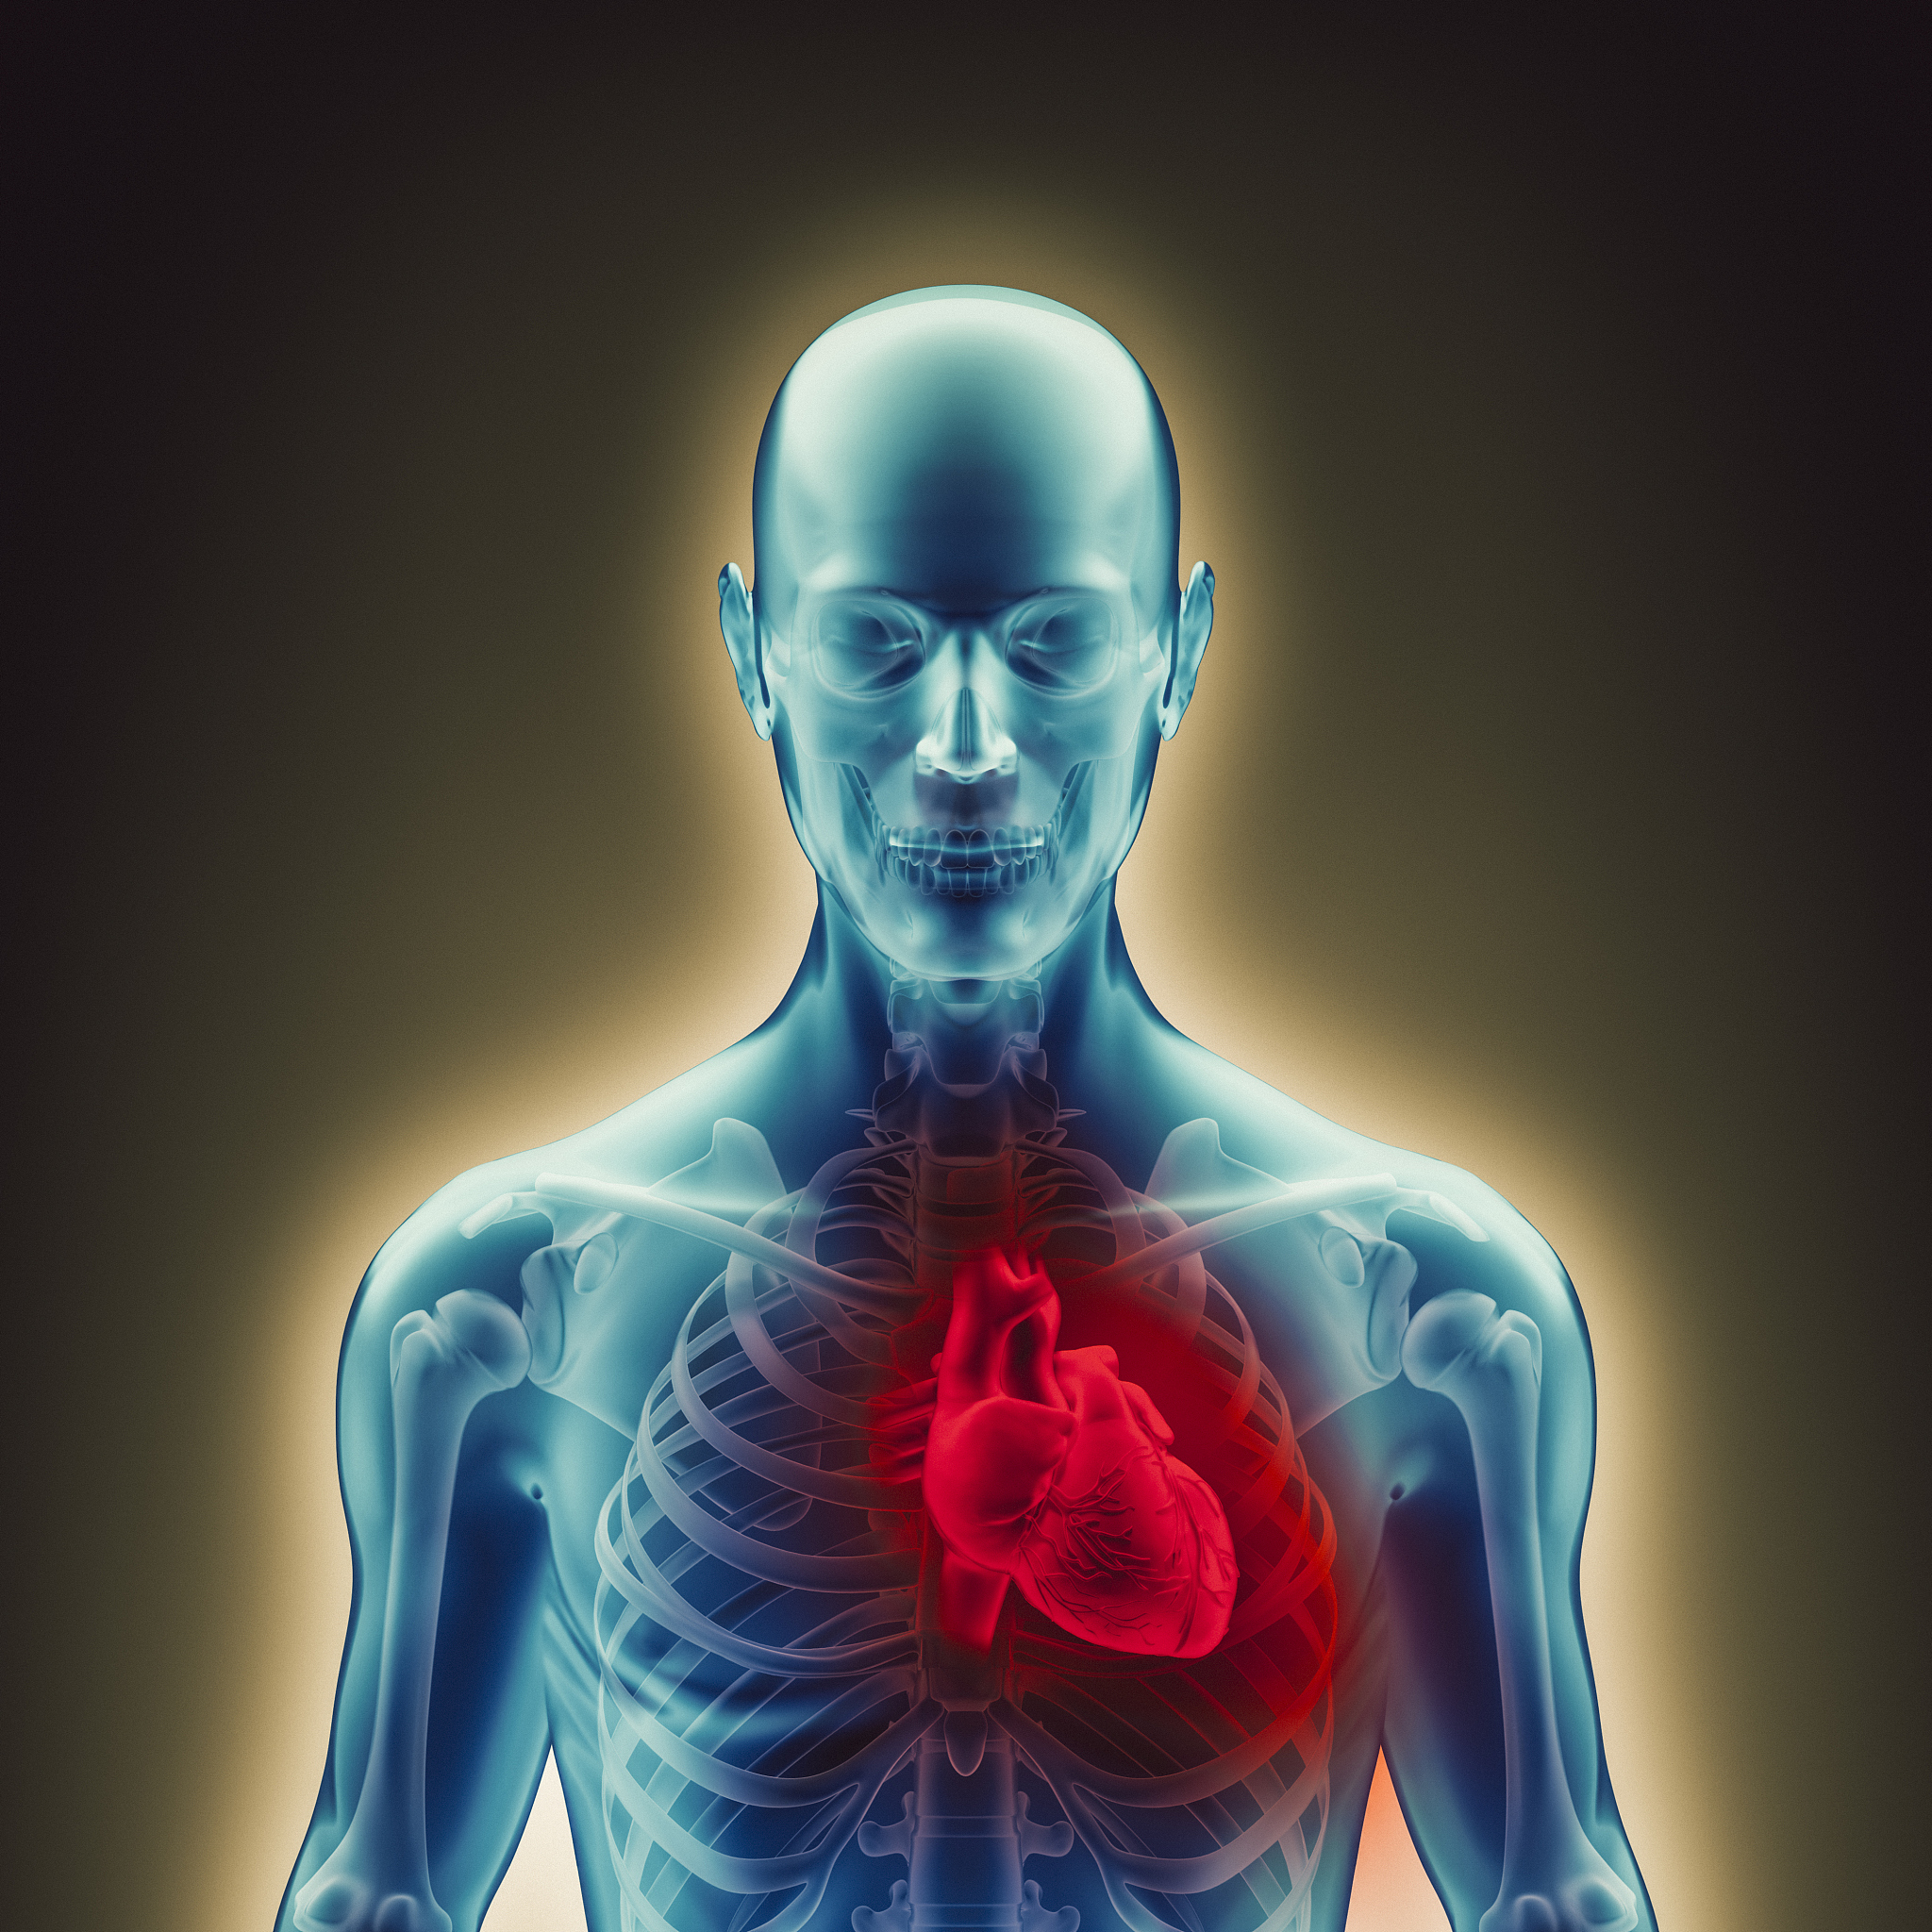

Coronary heart disease, also known as ischemic heart disease, is a medical condition that occurs when the blood vessels that supply blood to the heart become narrowed or blocked. This can lead to a heart attack or other serious complications if not treated on time. In this article, we will discuss the early symptoms of coronary heart disease that everyone should be aware of.

Chest pain or discomfort is the most common symptom of coronary heart disease. It is usually described as a tight or squeezing sensation in the chest that may spread to the arms, back, neck, jaw, or stomach. The pain may last for a few minutes or longer and may be triggered by physical activity or emotional stress.